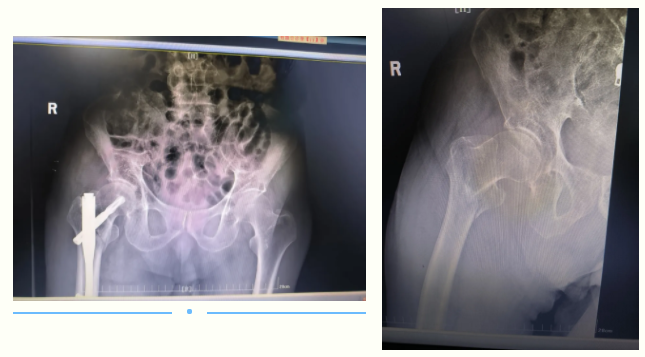

案例一:微创髓内针技术

景德镇市第一人民医院创伤中心接诊了

一名90多岁高龄摔伤患者

从患者家属口中得知

老人是在家中不慎摔倒

右臀部着地

关节活动受限

经X光片中明显看出

患者髋部严重骨折

考虑到患者的高龄和骨折的严重性

经过多学科专家的反复评估

决定由创伤急救中心骨科组副主任余万初主导

采用了微创髓内针技术

为老人行髋部骨折手术

具有时间短、创伤小、出血少等优点

有助于患者较快恢复

术后,经过20多天的悉心护理,

患者的病情逐渐稳定

并开始进行康复训练。

技术分享:髓内针内固定术是将大小、长短适合的髓针插置于骨折断端两侧的骨髓腔内,使骨折得以固定的手术。与传统的骨折固定方式——钢板固定相比,髓内钉可以控制骨折部位的轴向力线,防止骨折旋转畸形,降低内植物断裂的风险。同时,由于采取闭合及微创技术,能够有效降低手术感染率,减少术中出血,减轻病人痛苦,减少住院花费和住院时间。